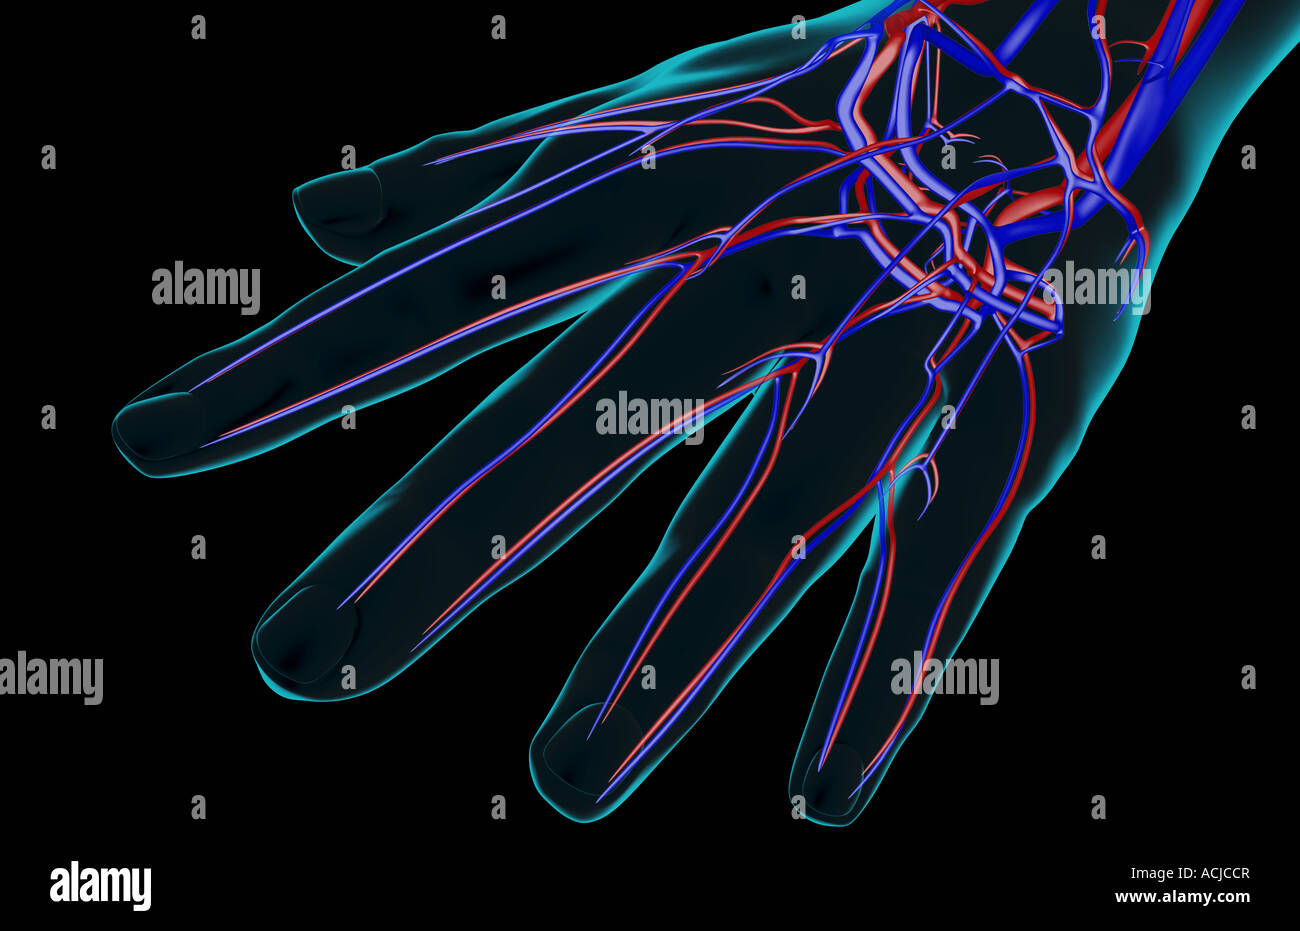

The blood supply of the hand Stock Photohttps://www.alamy.com/image-license-details/?v=1https://www.alamy.com/stock-photo-the-blood-supply-of-the-hand-13169110.html

The blood supply of the hand Stock Photohttps://www.alamy.com/image-license-details/?v=1https://www.alamy.com/stock-photo-the-blood-supply-of-the-hand-13169110.htmlRFACJCCR–The blood supply of the hand